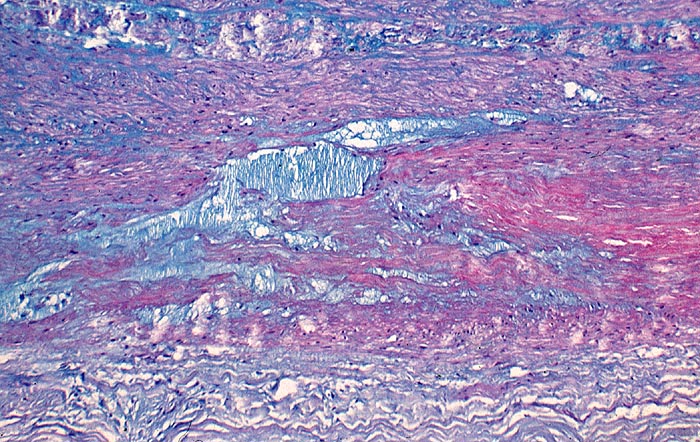

AP/ Zystische Mediadegeneration (Medianekrose)

Zystische Mediadegeneration (Medianekrose)

Aorta

Morphologie